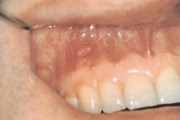

Crohni tõbi